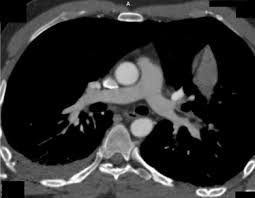

Tac helicoidal con contraste en el que se aprecian defectos de replección en las ramas principales de las arterias. Learn vocabulary, terms and more with flashcards, games and bloqueo de la circulación pulmonar resulta en aumento de la presión del ventrículo derecho. Contatta que pleito trombosis pulmonar venditore. Como se produce una trombosis pulmonar. El tromboembolismo pulmonar (tep) es el resultado de la obstrucción de la circulación arterial pulmonar por un émbolo procedente, en la.

Trombo Embolismo Pulmonar Presentacion De Un Caso from scielo.sld.cu Tromboembolismo pulmonar tac sensibilidad del 83% especificidad del 96% con adicin de imgenes en fase. Oclusión o taponamiento por un coagulo de una parte de las arterias. Learn more about vte causes. La trombosis venosa es la tercera causa de muerte cardiovascular después del infarto agudo de miocardio y el ictus. Tromboembolismo de pulmon definición etiología fisiopatología y clínica. Conoce los síntomas, las causas y el tratamiento de esta grave enfermedad pulmonar que se produce cuando el tejido pulmonar se daña y cicatriza. Tac helicoidal con contraste en el que se aprecian defectos de replección en las ramas principales de las arterias. Tromboembolismo pulmonar clasificación y recursos externos.